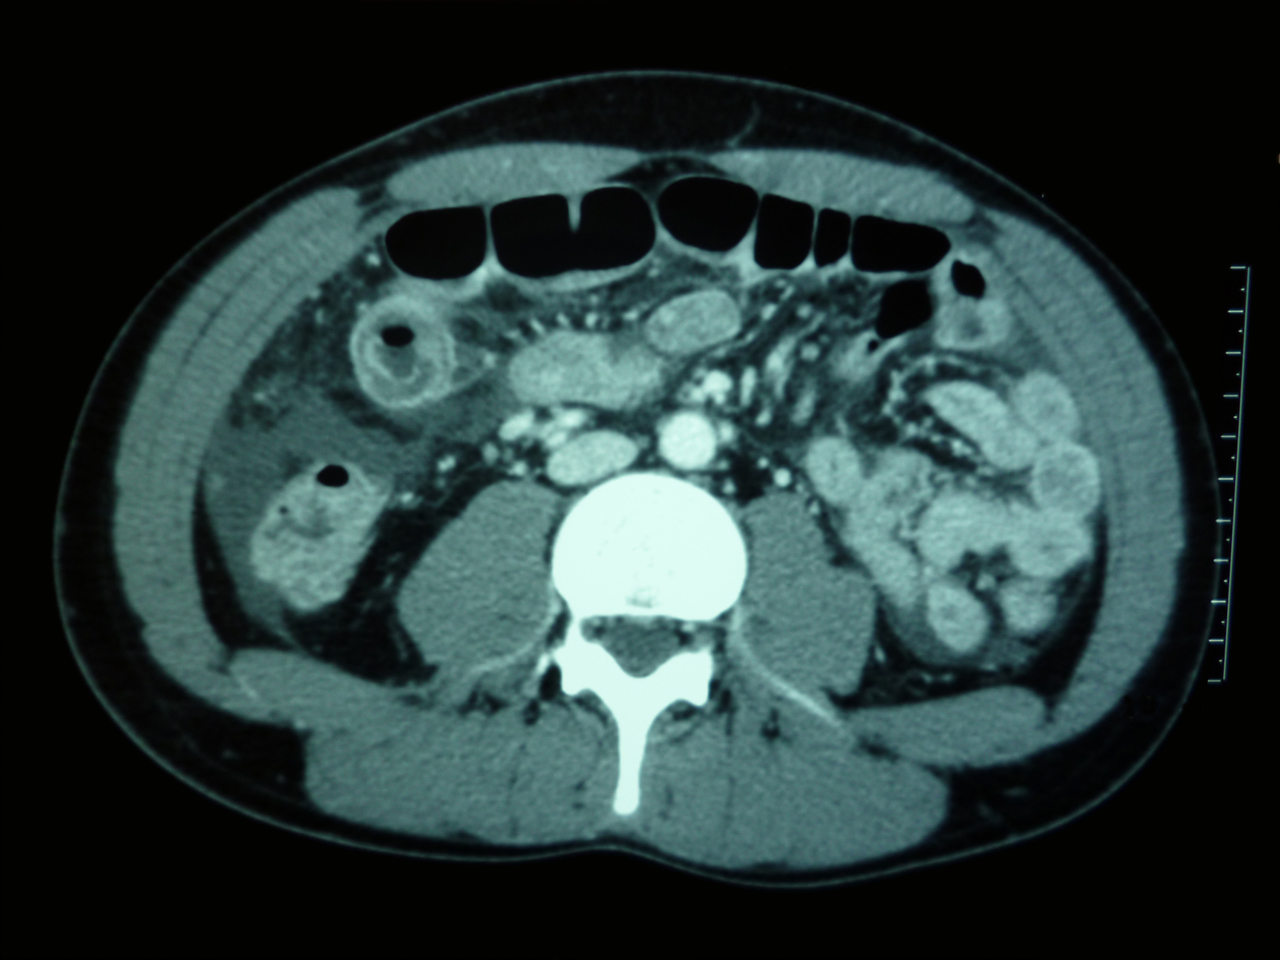

Quel est votre diagnostic ?

Il s'agit d'un angiœdème héréditaire.